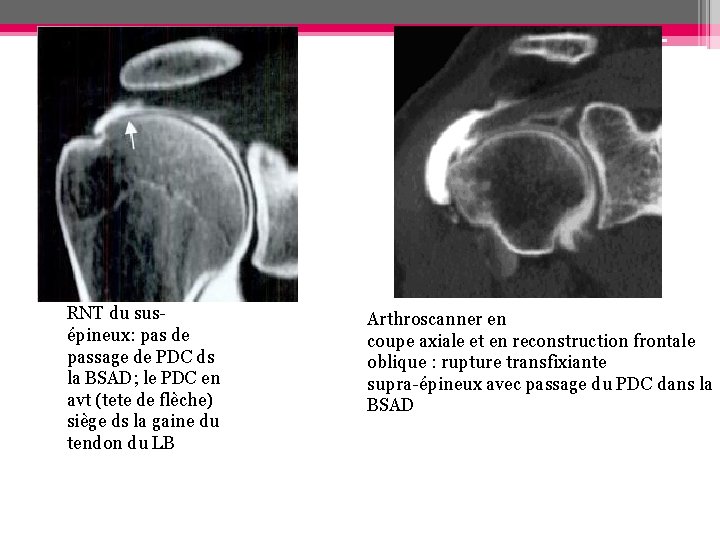

Arthroscanner - Topographie et extension exacte de la rupture + retentissement musculaire - BSAD: opacifiée: rupture transfixiante ou complète non opacifiée: RNT de la face articulaire des tendons - Points faibles: ◦ Ruptures tendineuses non communicantes ◦ Ruptures de la face bursale de la coiffe non détectables

RNT du susépineux: pas de passage de PDC ds la BSAD; le PDC en avt (tete de flèche) siège ds la gaine du tendon du LB Arthroscanner en coupe axiale et en reconstruction frontale oblique : rupture transfixiante supra-épineux avec passage du PDC dans la BSAD